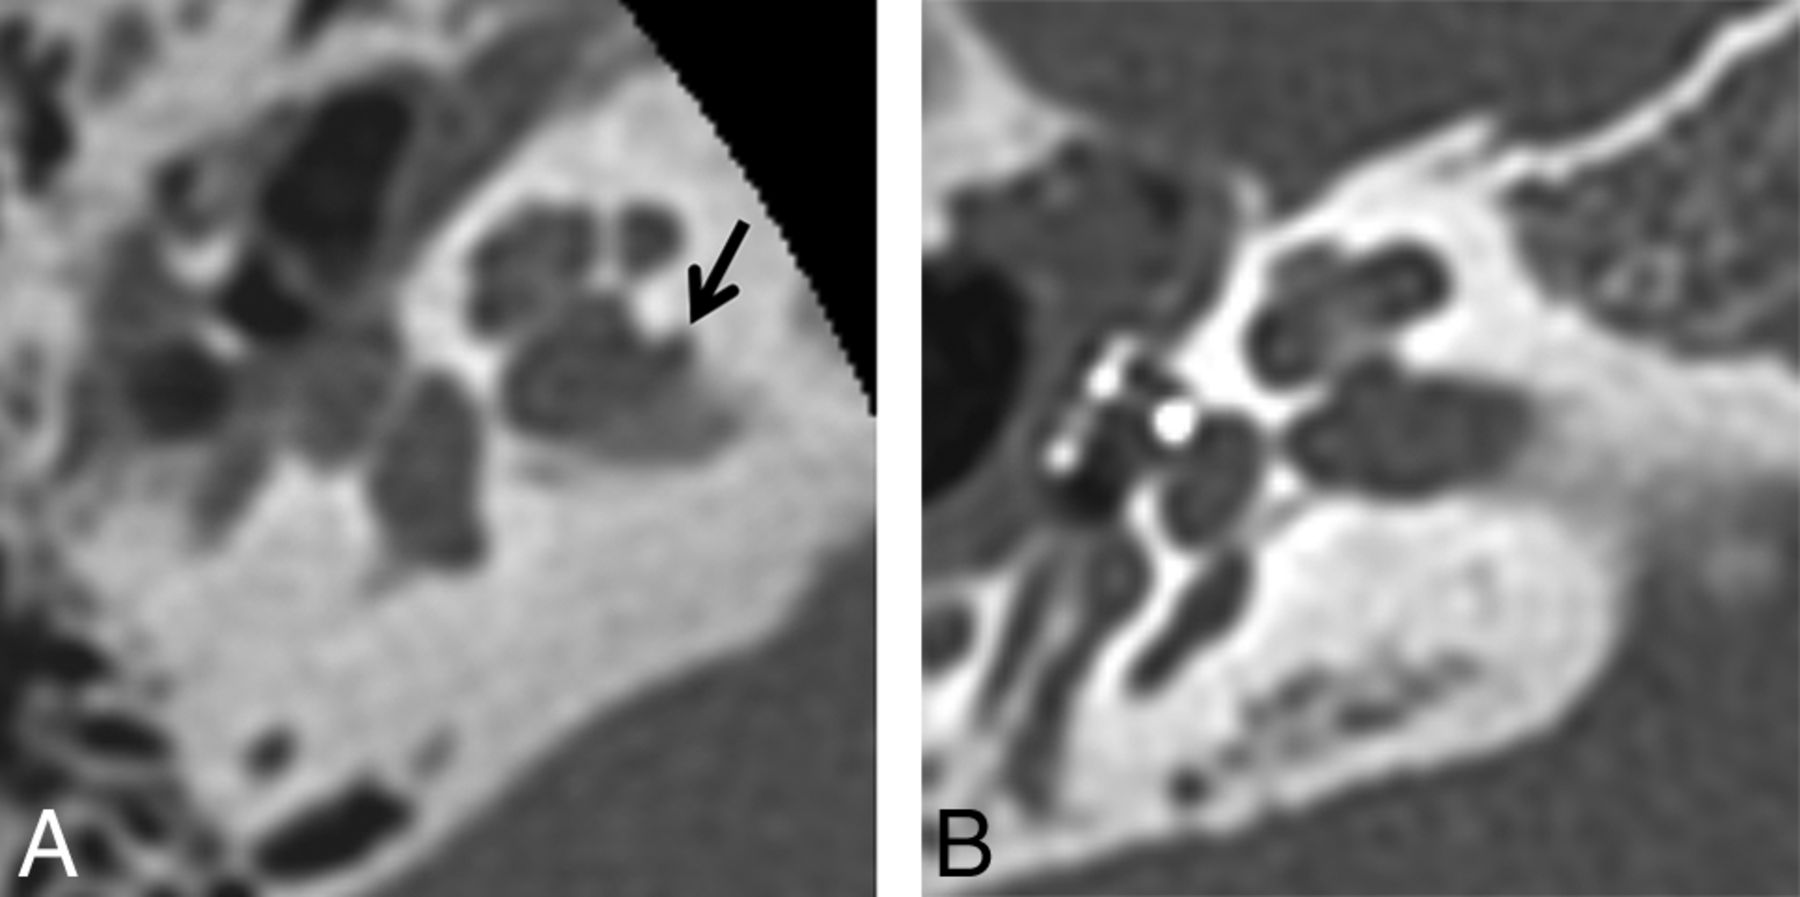

Four fellowship-trained neuroradiologists (3 years', 12 years', 4 years', and 6 years' subspecialty experience) served as readers for this retrospective study. Each reader participated in an initial image review as well as a subsequent image review. For both image reviews, the neuroradiologists were instructed to first assess the axial 0.625 mm bone algorithm images to determine the presence or absence of an IAC diverticulum (Fig 1). If necessary or desired, the coronal bone algorithm images could also be used to aid in making this determination. A subjective determination of the presence or absence of an IAC diverticulum was used rather than a minimum size threshold to be consistent with the described methods of Mihal et al,1 Puac et al,5 and Pippin et al.8 In addition to the initial and subsequent image reviews in which the 4 neuroradiologists participated, 1 of the neuroradiologists (3 years' subspecialty experience) reviewed the temporal bone CT images to determine the presence or absence of an enlarged vestibular aqueduct, labyrinthine dysplasia, cochlear cleft, and otospongiosis.

Axial temporal bone CT image (A) at the level of the inferior aspect of the right internal auditory canal demonstrates the typical appearance of an internal auditory canal diverticulum (arrow). An image obtained at the same level in a different patient without an internal auditory canal diverticulum is provided for comparison (B).